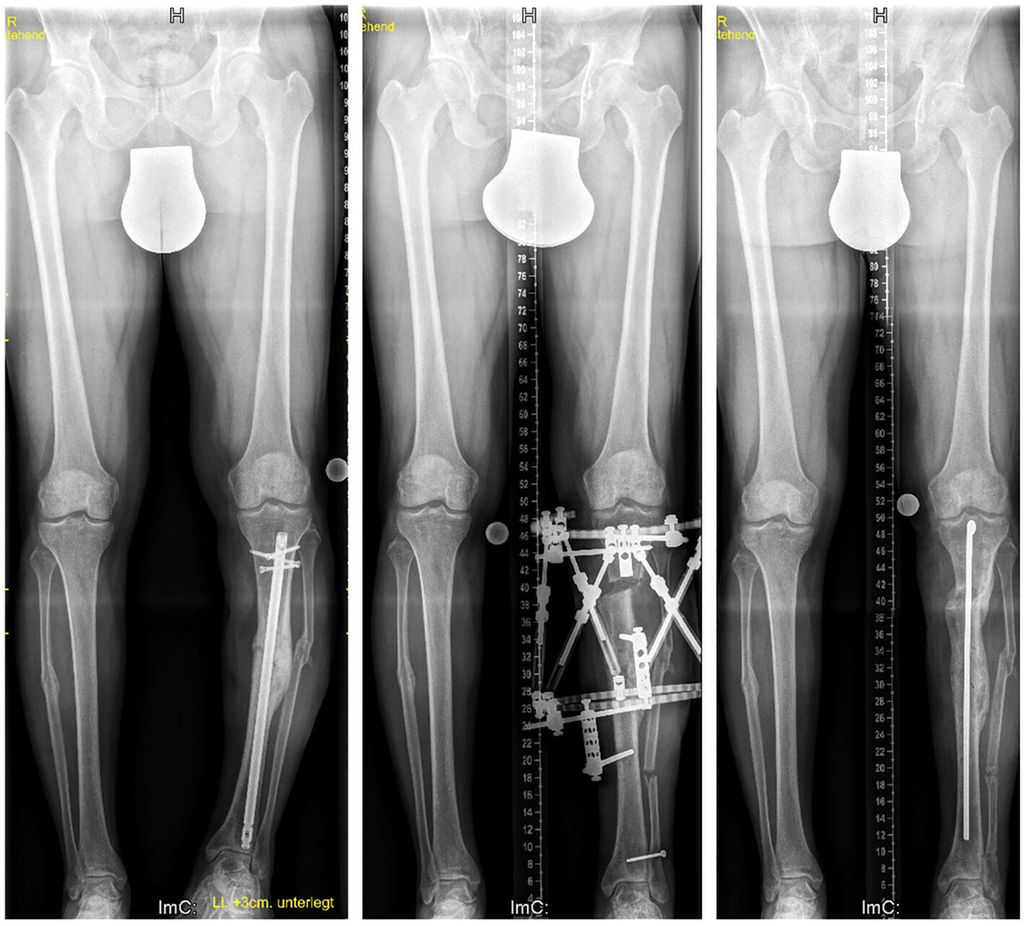

Bei Erwachsenen sind es ebenfalls erworbene und angeborene Fehlstellungen, wobei hier Pseudarthrosen (Abb. 4), infizierte Pseudarthrosen sowie nicht verheilte Arthrodesen am Fuß und Sprunggelenk hinzukommen. Bei der simplen Beinverkürzung ohne oder mit geringer Achsabweichung hat der Verlängerungsmarknagel (Precice®, Nuvasive Inc.) den externen Fixateur abgelöst. Dieser Verlängerungsmarknagel kann über einen antegraden Zugang am Oberschenkel ab dem 8.–10. Lebensjahr verwendet werden und über einen femoralen retrograden Zugang oder nach Fugenschluss an der Tibia eingesetzt werden.

Abb. 4: Dieser 42-jährige Patient erlitt eine offene Unterschenkelfraktur, die sich trotz initialen Fixateurs externe infizierte. Es erfolgten eine Lappenplastik und schließlich eine Osteosynthese mit Marknagelung. Bei der Vorstellung 4 Jahre nach dem initialen Trauma zeigten sich eine Varusfehlstellung und eine Beinverkürzung von 1,7 cm. Der Nagel wurde entfernt und eine Osteotomie proximal der ehemaligen Fraktur durchgeführt. Auch in diesem Fall wurde nach Apparatabbau ein Rush-Pin zur weiteren Stabilisierung eingebracht. Die Beinlänge und Beinachse konnten vollständig korrigiert werden